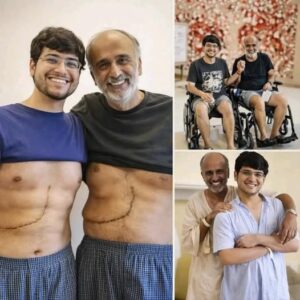

El conmovedor caso del hijo que salvó a su padre con una donación de hígado

El texto habla sobre las historias virales en redes de hijos que le donan un cacho de hígado a sus papás. Aunque el internet le echa mucha…